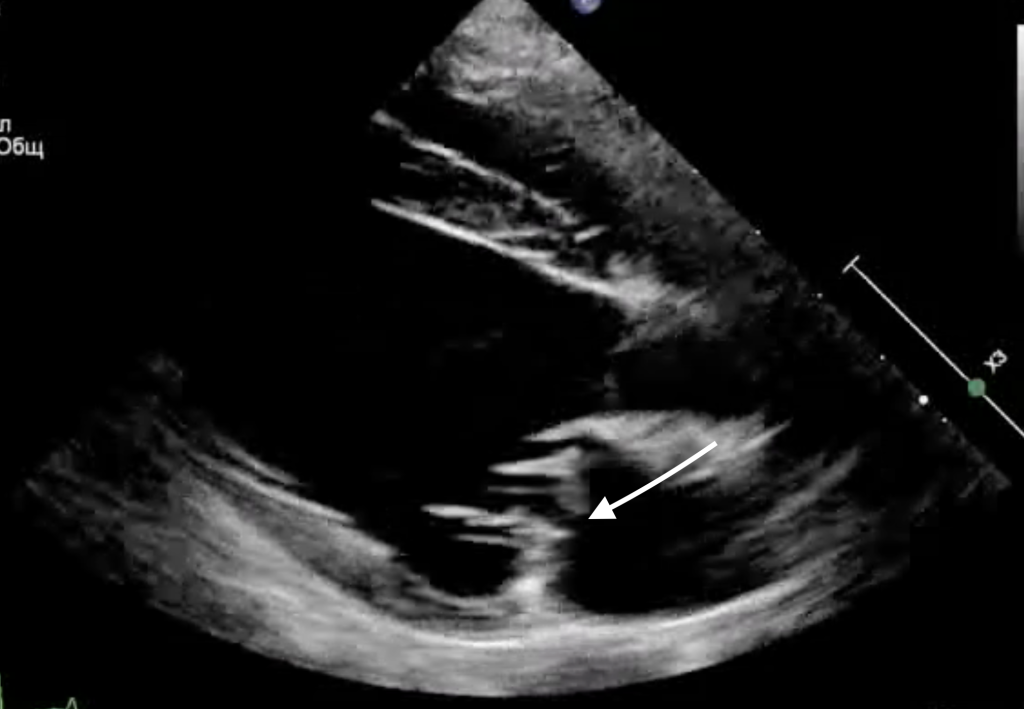

Эхокардиографическое исследование выявило пролапс передней створки митрального клапана в сегменте А2, обусловленный отрывом хорд первого порядка (фото 1, 2). Этот дефект приводил к тяжелой митральной регургитации, что проявлялось одышкой, кашлем, снижением физической активности пациента.В связи с этим было принято решение о проведении хирургического лечения, включающего аннулопластику митрального клапана и коррекцию пролапса створки по методу Альфиери.